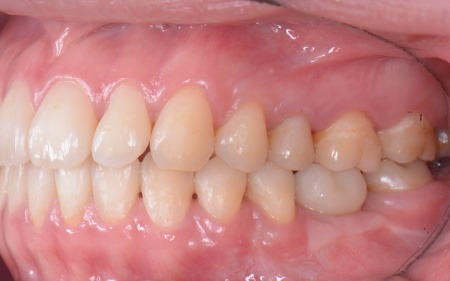

20代女性 歯の根が割れた歯を抜歯したあと矯正治療と骨再生を併用したインプラント治療で補った症例

また、上下の歯を噛み合わせた際に前歯が噛み合わず隙間ができる開咬(かいこう)と呼ばれる噛み合わせも見られました。

開咬は奥歯に負担が集中しやすく、その影響で今回のように歯の根が割れてしまった可能性が高いと考えられます。

まず、右上と左下の奥歯を抜歯しました。

その後、全体の噛み合わせを改善するため、矯正治療を開始しています。